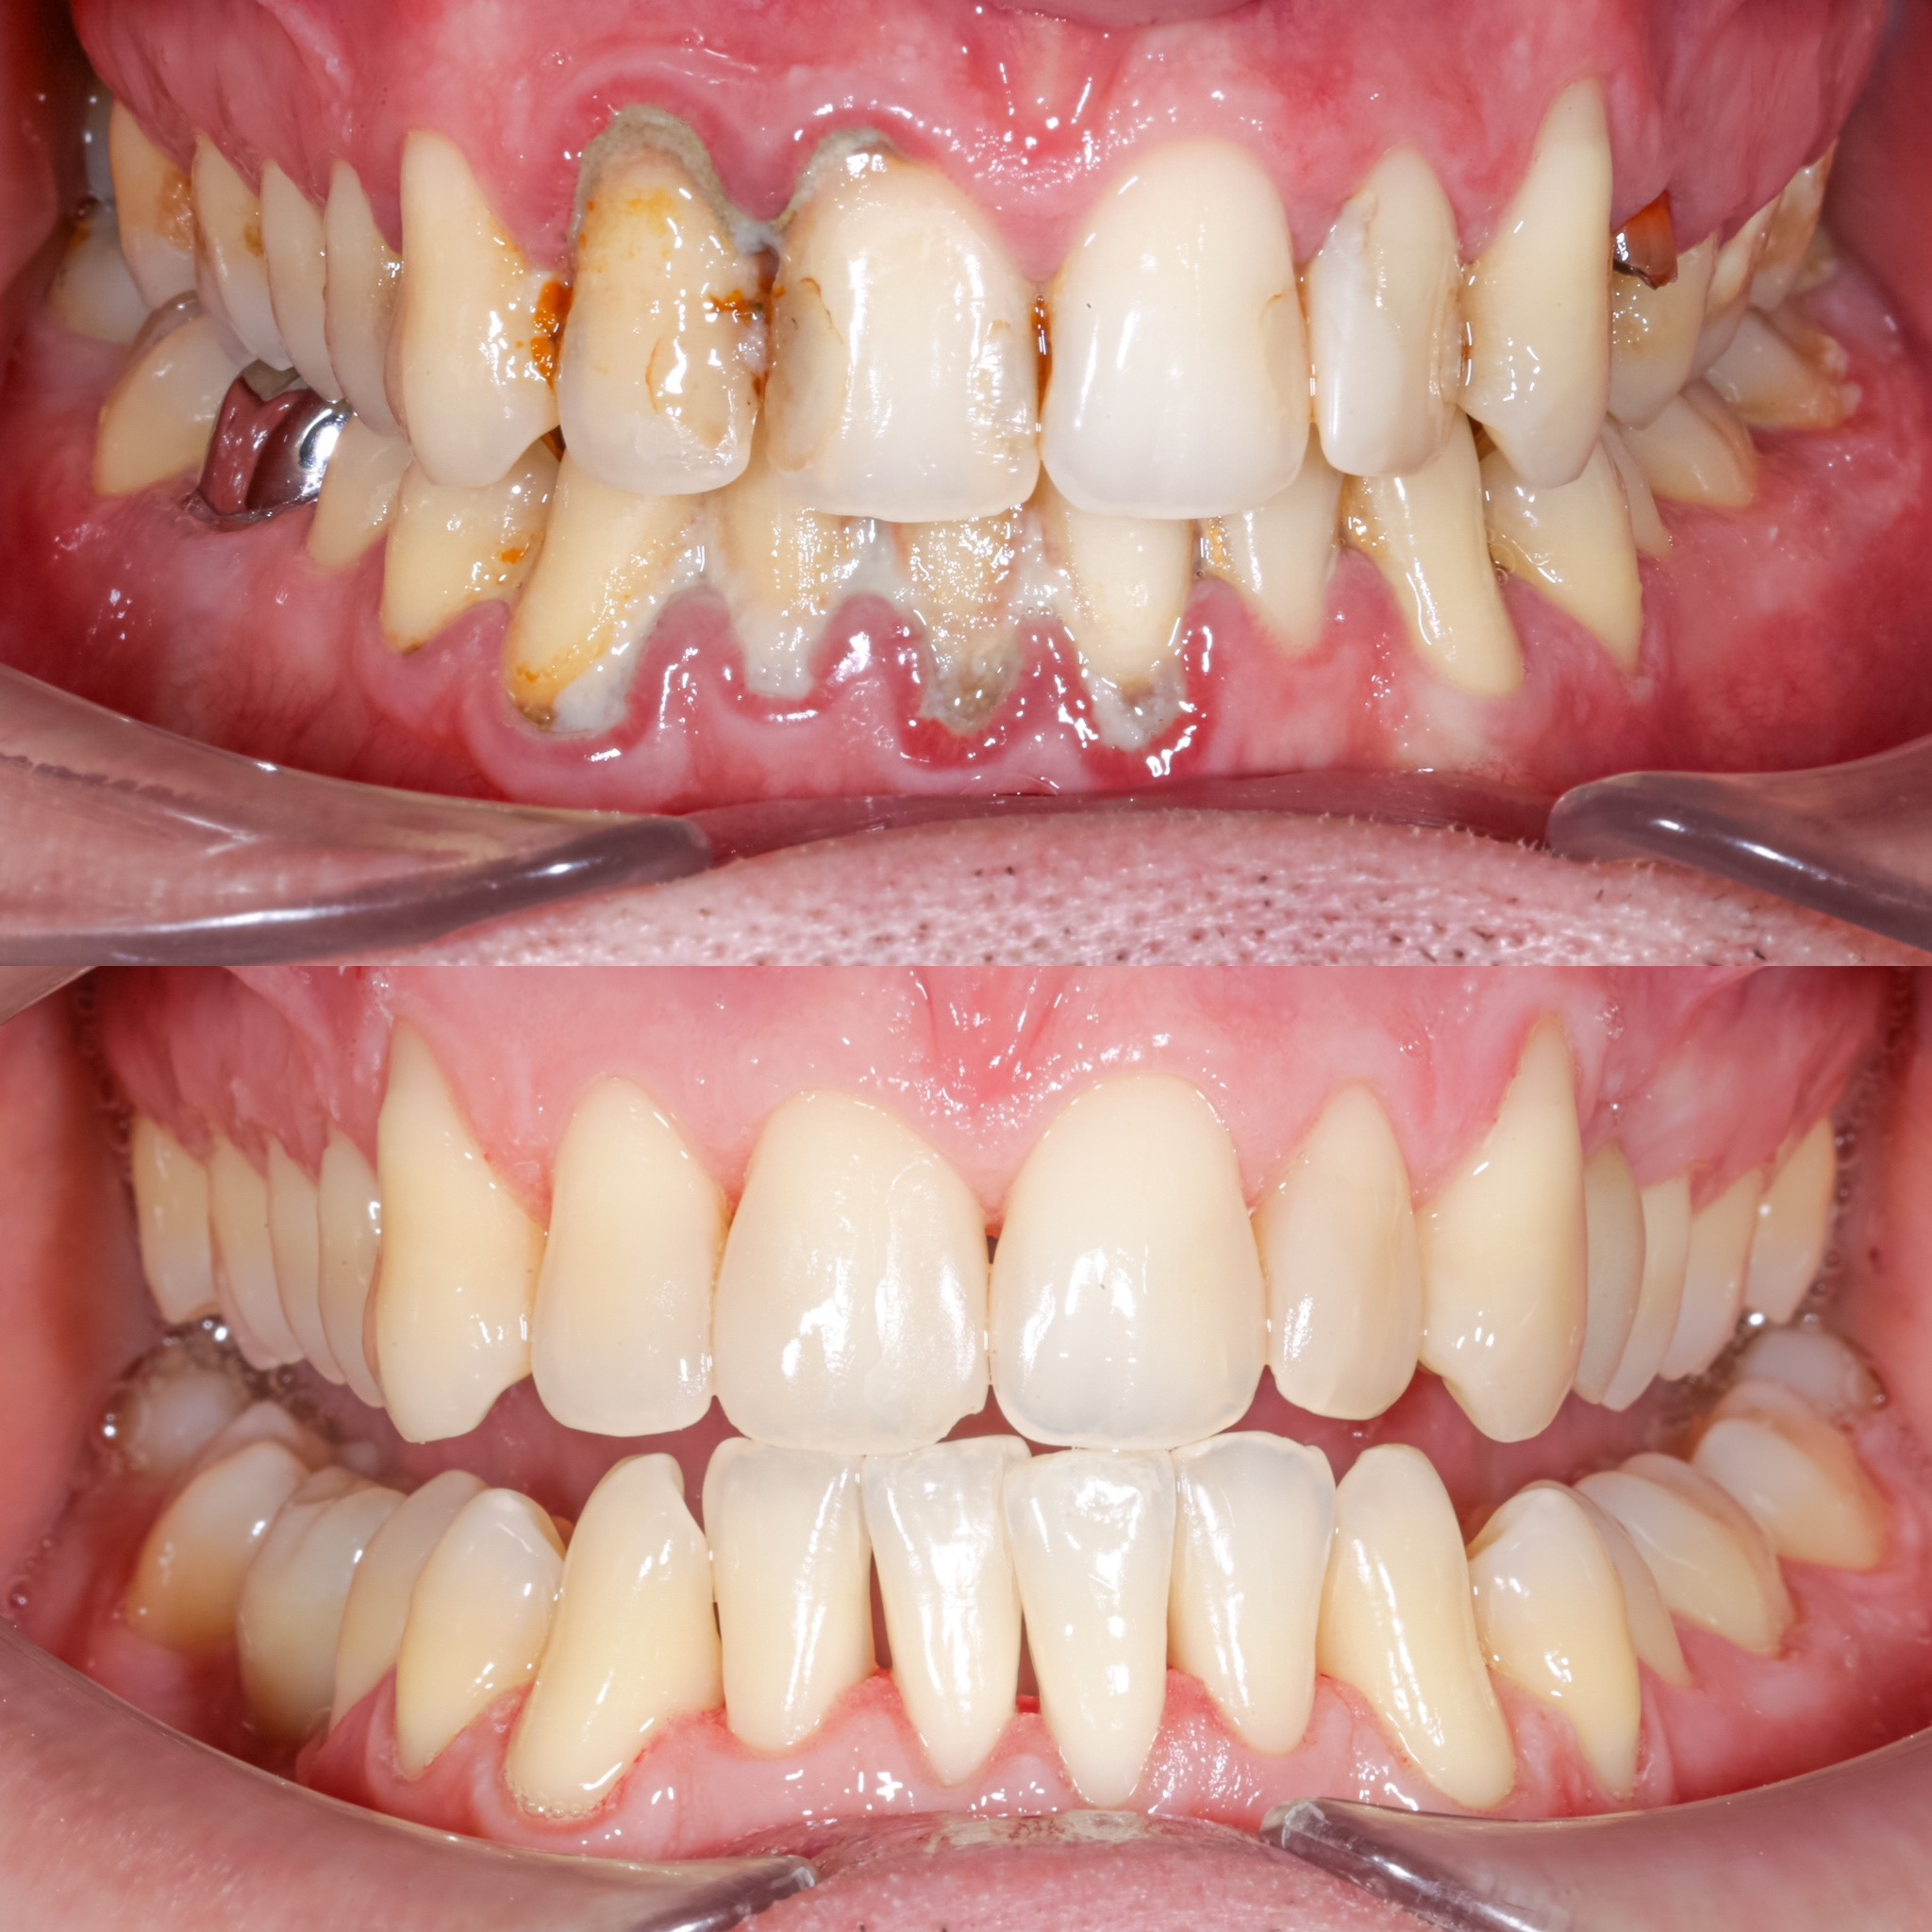

Галерея

Професійна гігієна (чистка) зубів складається з кількох етапів

Ультразвукова чистка зубів

Зубний камінь, в залежності від місця утворення, поділяється на над- та підясенний. Найбільшу небезпеку для здоров'я зубів становить другий тип, адже це дуже сприятливе середовище для шкідливих бактерій.

При проведенні професійної гігієни застосувується ультразвуковий скалер, що дозволяе видалити зубний камінь разом з хвороботворними бактеріями з підясенних кишень.

Повітряно-абразивна чистка зубів (Air Flow)

Завдяки піскоструменевому апарату з технологією Air Flow, який використовуючи тиск повітря та води, подає на зубну емаль спеціальний абразивний склад, зуби можна очистити не лише від м’якого нальоту, а й від пігменту. Для видалення нальоту, в Космічній стоматології Драганчука ми використовуємо KaVo prophy pearls supragingival calcium carbonateneutral.

Чистка зубів щіточками та пастами

Фінальний етап професійної гігієни - полірування спеціальними щіточками та пастою, щоб усунути мікротріщини та шорохуватості, що виникли після чистки та видалити залишки нальоту, що могли в них залишитись. Це дозволяє суттєво уповільнити формування нових відкладень.

Полірування зубної емалі гумками

Кінцеве полірування поверхні зубів проводиться із застосуванням різних насадок, зокрема спеціальних гумок, що надає зубам ідеальної гладкості та блиску. Спеціальні гумові насадки відмінно справляться з наданням естетичної довершеності твоїй посмішці.